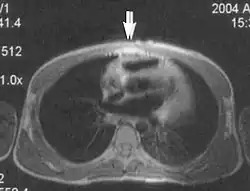

Metal artifacts

Metal artifacts occur at interfaces of tissues with different magnetic susceptibilities, which cause local magnetic fields to distort the external magnetic field. This distortion changes the precession frequency in the tissue leading to spatial mismapping of information. The degree of distortion depends on the type of metal (stainless steel having a greater distorting effect than titanium alloy), the type of interface (most striking effect at soft tissue-metal interfaces), pulse sequence and imaging parameters. Metal artifacts are caused by external ferromagnetics such as cobalt containing make-up, internal ferromagnetics such as surgical clips, spinal hardware and other orthopaedic devices, and in some cases, metallic objects swallowed by people with pica.[3] Manifestation of these artifacts is variable, including total signal loss, peripheral high signal and image distortion (Figs 3 and 4).[1] Reduction of these artifacts can be attempted by orientating the long axis of an implant or device parallel to the long axis of the external magnetic field, possible with mobile extremity imaging and an open magnet. Further methods used are choosing the appropriate frequency encoding direction, since metal artifacts are most pronounced in this direction, using smaller voxel sizes, fast imaging sequences, increased readout bandwidth and avoiding gradient-echo imaging when metal is present. A technique called MARS (metal artifact reduction sequence) applies an additional gradient, along the slice select gradient at the time the frequency encoding gradient is applied.